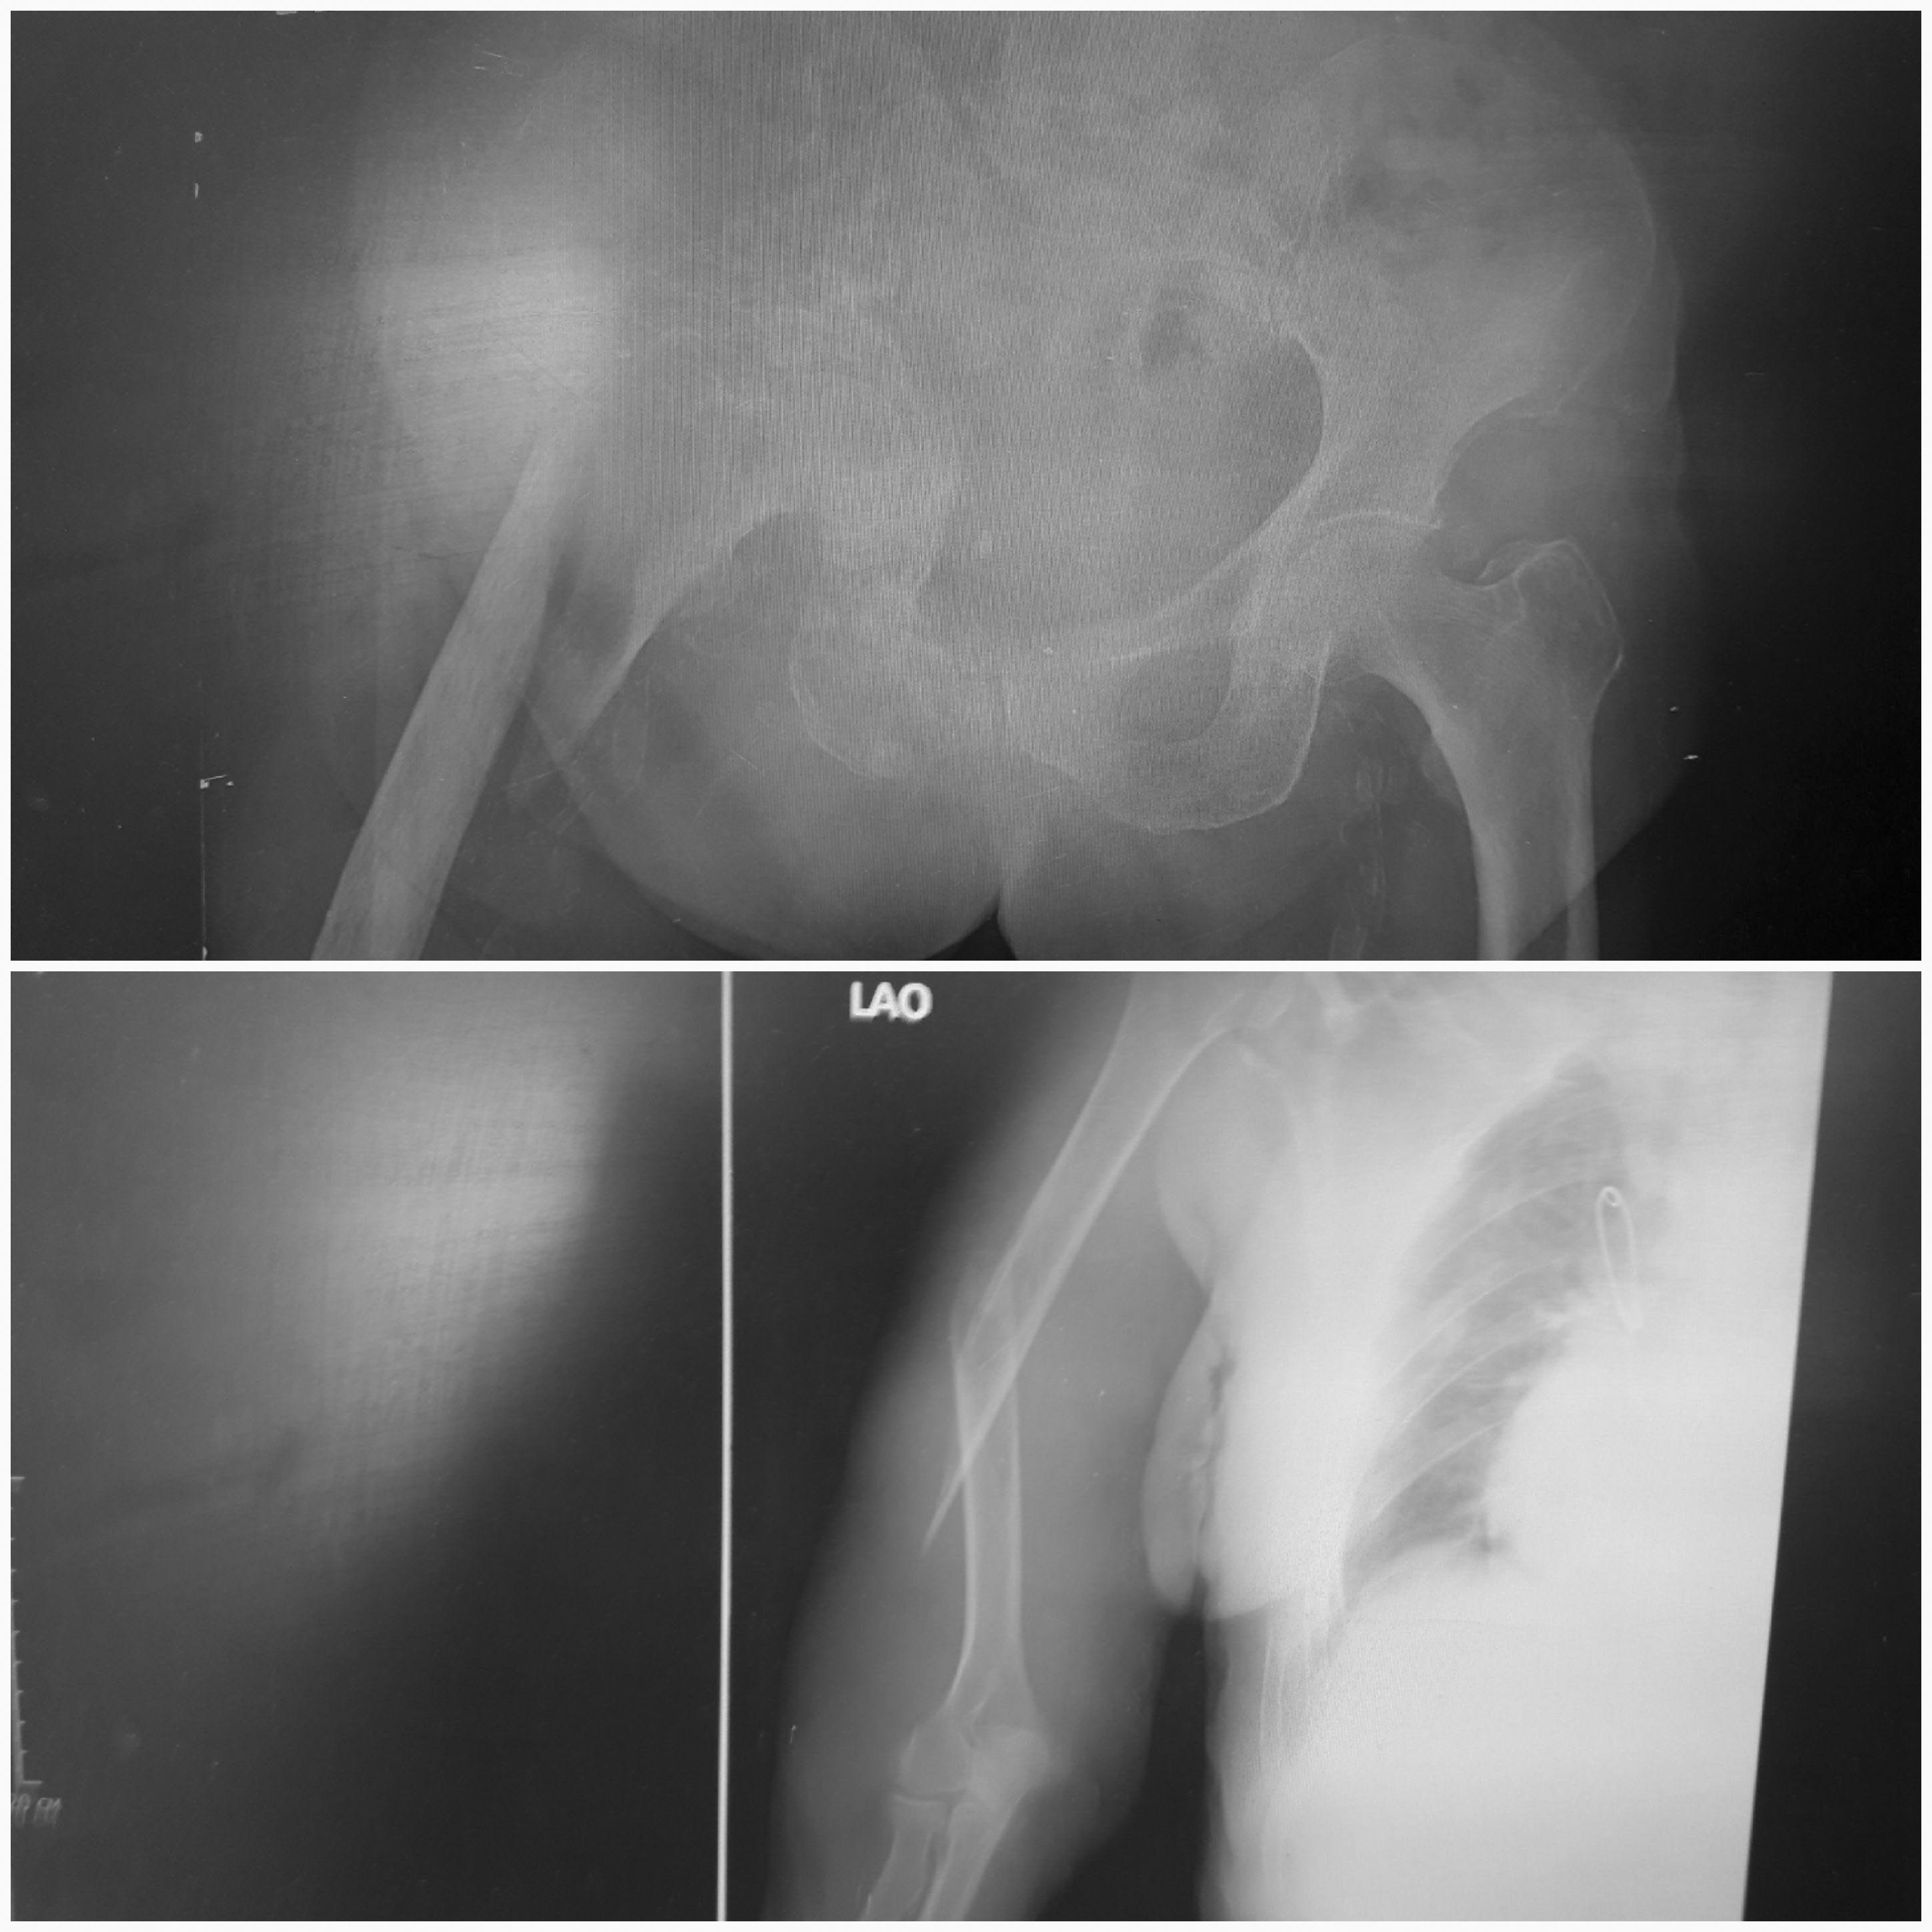

Перелом подвертельный винтообразный бедренной кости справа на фоне застарелого неоартроза и центрального вывиха правого бедра( качество снимка страдает) на фоне остеолитических изменений в костях таза и др. костях.Cr mammae, симптомат.лечение получает. + "винт"диафиза правого плеча справа. Есть когнитивные нарушения не выраженные, фибрилляция предсердий, легкие левосторонний компенсированный гемипарез. До травмы, со слов родственников ходила "на руках", "в позе гориллы"(сохранена оригинальная речь) по квартире. Первый вариант сразу-не трогать, не оперировать, сменился размышлениями, а дальше-что?Если этапно оперировать, что в первую очередь? И каким образом синтезировать бедро, которое упирается б.вертелом в таз?

На бедре и плече признаки остеопороза и остеомаляции (паралитическая сторона). Наиболее актуальным вижу интрамедуллярную фиксацию - гаама на бедро и стержень в плечевую кость... Но, в условиях тотальной ковидной сегрегации вряд ли найдутся герои...

Какой способ установки гамма-стержня Вы предлагаете при таких особенностях анатомии проксимального бедра?

Спасибо! Да, гамма не зайдет. Осталось только ретроградное введение. Думаю, что в данном случае